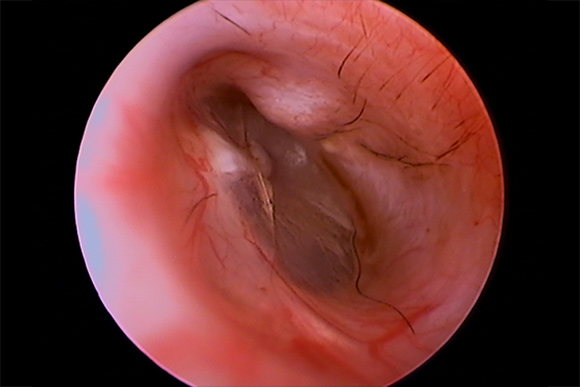

耳内視鏡(ビデオオトスコープ)で見た耳の状況

軽度~重度の症状の耳

犬の耳 1

犬の耳 1 犬の耳 2